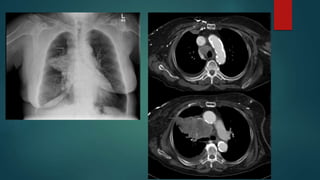

Superior Vena Cava Syndrome